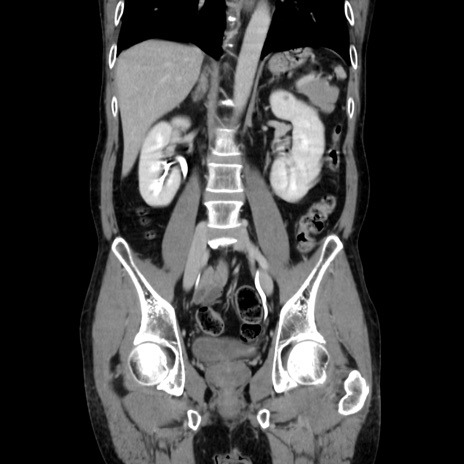

症例37(冠状断像)

【症例】40歳代 男性

【主訴】腹痛

【現病歴】4時間ほど前に電車に乗車中に臍部上より腹痛出現。徐々に増悪し起立困難となり、救急外来受診。生ものは数日食べていない。今朝お雑煮を食べた。

【身体所見】BT 36.8℃、BP 117/84mmHg、HR 91/min、SpO2 97%、苦悶様、腹部:臍上部広範囲圧痛あり、反跳痛±

【データ】WBC 8100、CRP 0.03